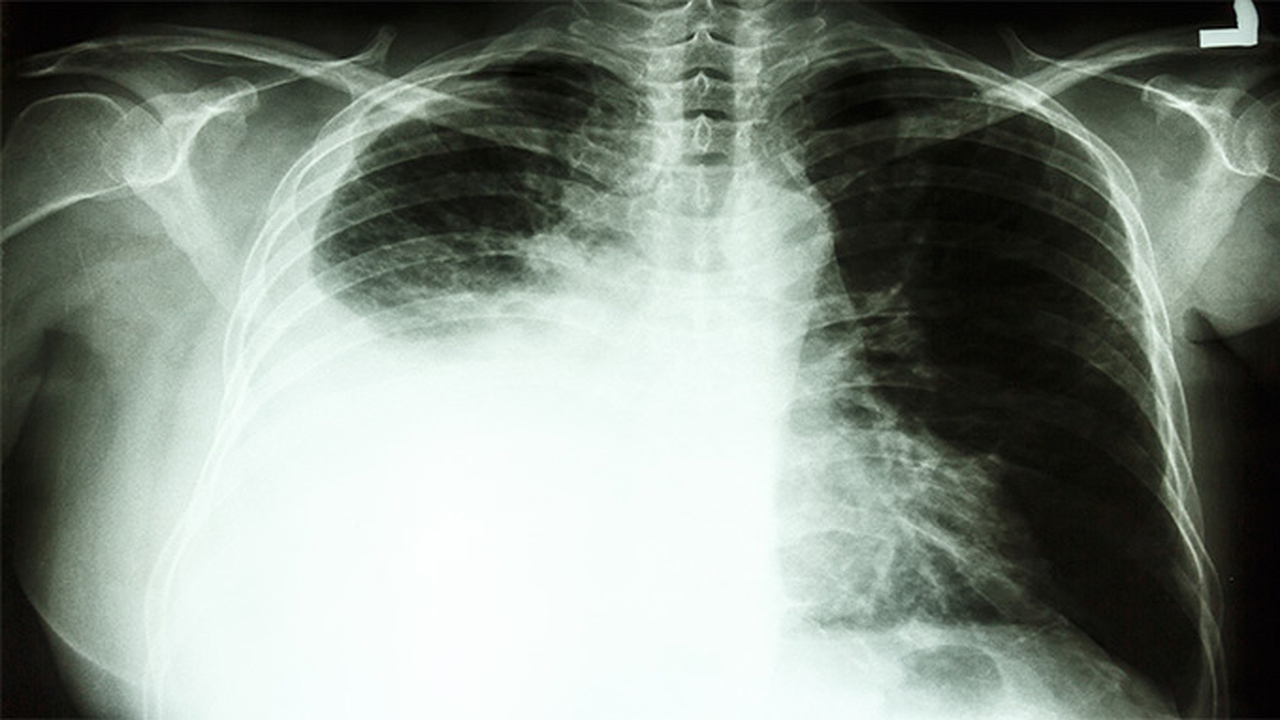

肺癌作为我国发病率较高的恶性肿瘤之一,其发病原因复杂多样,包括吸烟、空气污染、职业暴露以及遗传因素等。早期诊断和规范治疗对提高患者生存率至关重要。